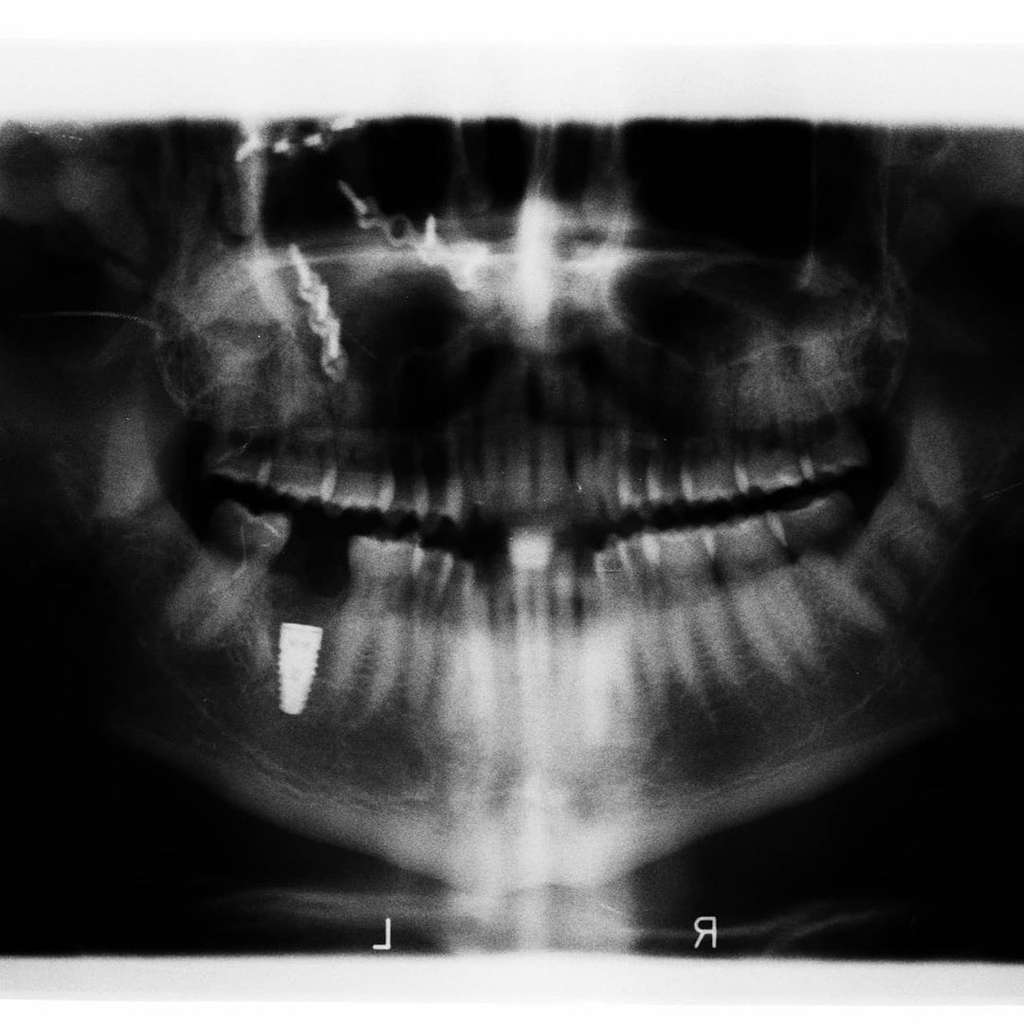

Dream - Hamish Daud membagikan hasil foto x-ray tengkoraknya ke Instagram. Pada bagian kepala, tepatnya dekat pelipis sampai ke tulang atas pipi, terlihat beberapa baut yang terpasang.

Sementara, pada bawah rahang juga terlihat terpasang satu baut. Suami Raisa Andriana itu mengatakan ada beberapa baut terpasang di kepalanya.

" Ketika orang mengatakan kepadaku bahwa aku kehilangan beberapa baut di kepalaku, aku biasanya setuju dengan mereka," ujar Hamish Daud dalam keterangan fotonya dikutip Dream dari akun instagramnya, Sabtu 27 Juni 2020.

Sontak saja, unggahan Hamish Daud yang menunjukkan kepalanya penuh baut itu langsung dipenuhi ragam reaksi warganet. Banyak warganet yang terkejut dan mengaku ngilu melihat penampakan foto X-Ray tengkorak ayah satu anak itu.